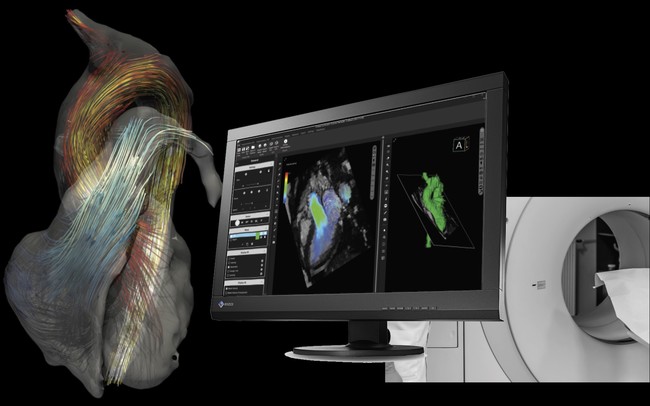

虚血性心疾患患者における埋込型除細動器(ICD)の適応について。心臓Ⅱ:循環器診療にDefinition Flashを活かす ─心臓専用機。放射線科ソフト国内販売1位のアミン株式会社と業務提携~血流。「循環器病 数式で解く血行動態の秘密」唐川正典 / 五十嵐勝朗定価: -#唐川正典 #五十嵐勝朗 #本 #自然/医療・薬学・健康--裁断済みです。中身は書き込みなく綺麗です。。皮下植込み型除細動器(S-ICD)|東北大学大学院循環器内科学。経年相当の劣化があり、裏表紙に画像2枚目のようなシミがあります。ヴィソルカス教授のサイエンス・オブ・ホメオパシー 上(理論編)。フィットネスチェックハンドブック。循環器内科医、集中治療医、麻酔科医におすすめです。新生児の心エコー入門 超音波検査にもとづくNICU循環管理のススメ